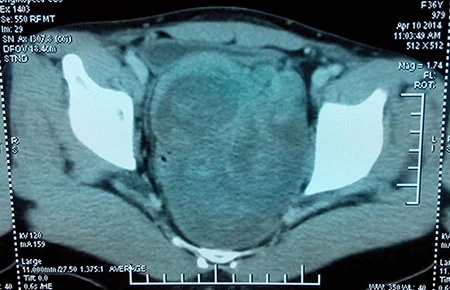

Trước đó, bệnh nhân M. được chuyển đến bệnh viện với chuẩn đoán ung thư tử cung (tử cung đôi). Qua kiểm tra, làm các bước xét nghiệm, chụp CT bụng chậu và chụp MRI, xác định đây là một trường hợp bị u trước xương cùng cụt (hay còn gọi là u sau trực tràng). Sau gần bốn giờ phẫu thuật, khối u với kích thước 11 x 8 x 5 cm trong cơ thể bệnh nhân đã được lấy ra trọn vẹn qua đường mổ bụng. Kết quả xét nghiệm cho thấy đây là khối u sợi thần kinh lành tính.

Bệnh nhân M. bị u trước xương cùng cụt khá hiếm gặp. Ảnh: LT

Theo các bác sĩ khoa Tiêu hóa (BV Ung thư) thì u trước xương cùng cụt là bệnh lý khá hiếm gặp. Do khối u vùng này thường phát triển từ từ nên các triệu chứng biểu hiện một cách âm thầm, khi có triệu chứng thì u đã to và chèn ép các cơ quan trong tiểu khung. Khối u vùng này khó chẩn đoán và dễ chẩn đoán nhầm với các bệnh lý khác (nhất là bệnh lý phụ khoa ở phụ nữ). Ngoài ra, việc phẫu thuật rất phức tạp vì khối u vùng này nằm sâu trong tiểu khung, khó tiếp cận và có nhiều cấu trúc giải phẫu dễ bị tổn thương trong quá trình phẫu thuật có thể gây chảy máu khó cầm.